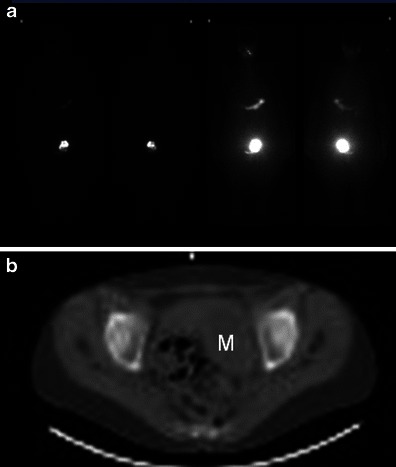

Scintigraphy

Scintigraphy performed with either iodine-123 or iodine-131 [22] is useful for diagnosing a hyperfunctioning struma ovarii on the basis of higher uptake of the radionuclide by the ovarian mass compared with the thyroid gland (Fig. 2).

Fig. 2.

a Whole-body I-123 imaging shows significantly increased I-123 uptake within the left hemi-pelvis in a 61-year-old woman with a history of thyrotoxicosis treated with radioiodine treatment twice over the last 30 years, who ultimately had a thyroidectomy which showed Graves disease but who remained thyrotoxic post surgery. b The area of increased uptake within the left hemi pelvis corresponds on the low-dose CT to an 8-cm left-sided pelvic mass (M) in keeping with a confirmed struma ovarii